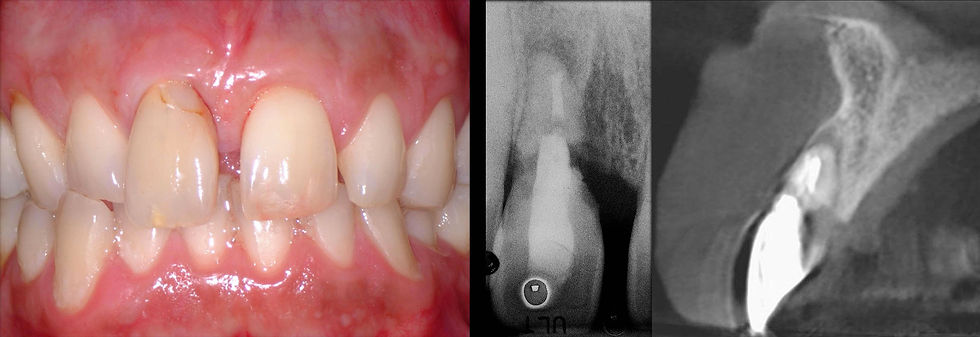

46 years old male patient with evident damage on the element 1.1, which had undergone a series of endodontic and conservative treatments over time due to a trauma suffered many years before. From the clinical and radiographic examination, the impossibility to recover this natural element and the need to intervene with an implant therapy are evident.

The clinical image shows an external cervical root resorption, from the radiograph and from the CBCT it is evident that the natural tooth is hopeless and that an implant therapy is needed. Given the presence of an evident diastema, an immediate provisionalization post-extraction approach is chosen in order to reduce as much as possible the timing and the discomfort for the patient.